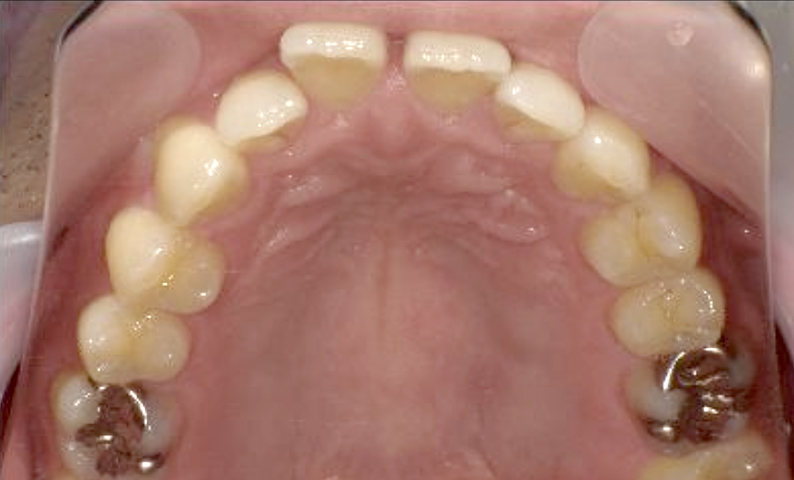

症例_003 上顎だけの部分矯正

治療期間:9ヶ月金額:30万円+税女性前歯のガタガタ八重歯上の前歯だけ

| Before | After |